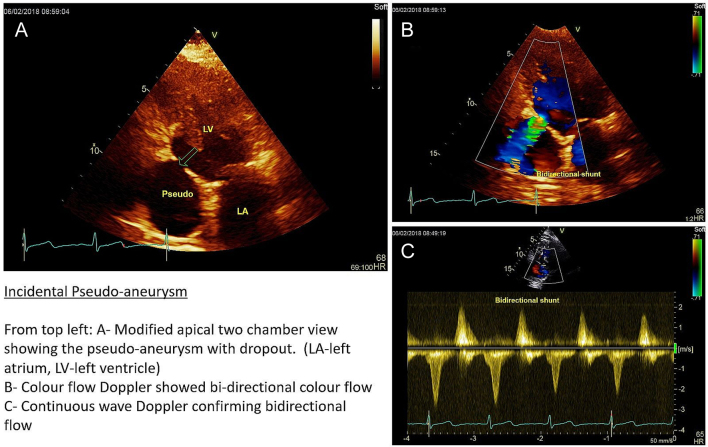

Echocardiogram performed 2 months after the second admission (and 6 months after index STEMI) surprisingly showed a basal inferior wall pseudo-aneurysm, with myocardial rupture sealed by pericardium (Fig. 1).

Figure 1.

Modified two-chamber view showing the pseudo-aneurysm with dropout. Color flow and Doppler showed the shunt was bi-directional.